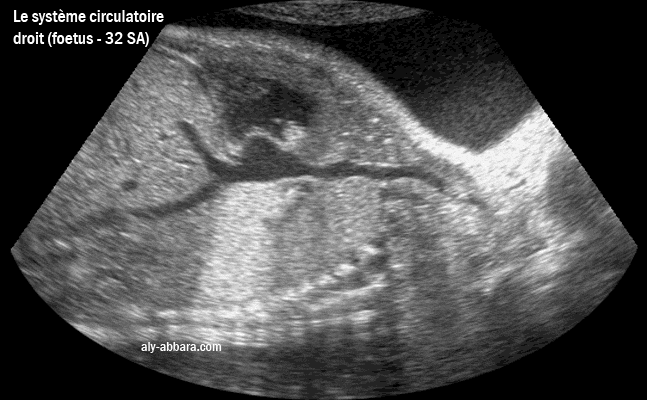

Image échographique montrant le cœur droit avec son oreillette droite, sa valve tricuspide et son ventricule droit, puis le retour veineux par la veine cave supérieure et la veine cave inférieure et les veines sus-hépatiques. Fœtus de 32 semaines d'aménorrhée |